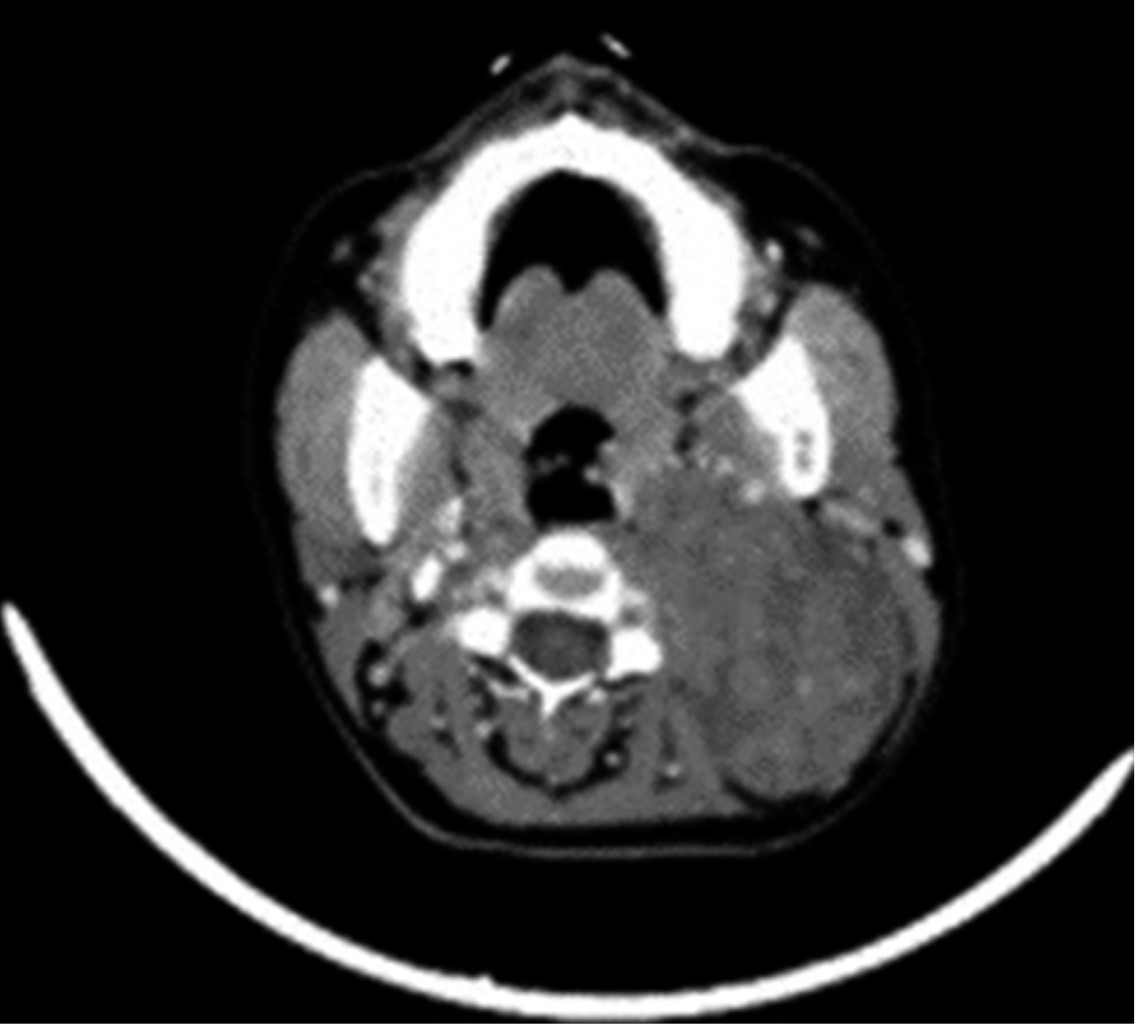

Sin datos de síndrome de respuesta inflamatoria sistémica, inestabilidad hemodinámica o compromiso cardiopulmonar, como complemento diagnóstico se solicita tomografía computarizada, la cual reporta gran masa redondeada de aspecto sólido de bordes regulares, bien delimitados, heterogénea de predominio hipodensa, con pequeñas zonas de menor densidad en su interior, sin identificar calcificaciones, con una densidad entre 24 y 37 UH y que posterior a la administración de medio de contraste intravenoso presenta una densidad entre 33 y 87 UH, localizado en nivel parafaríngeo izquierdo de 6.6 × 7.5 × 9.2 cm, lesión de espacio parafaríngeo izquierdo con sospecha de quiste branquial versus adenoma pleomorfo versus quiste branquial hemorrágico (Figuras 2, 3 y 4).

Figura 4